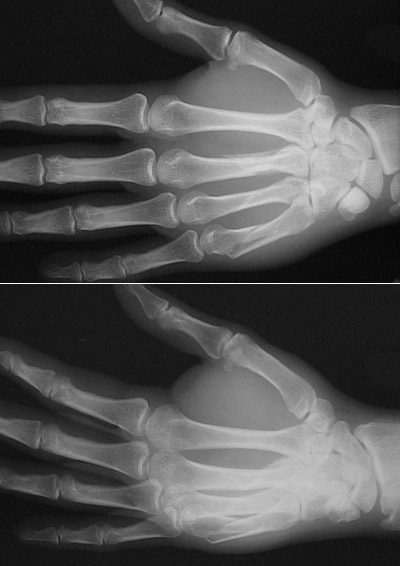

Click on the fracture in the radiograph above:

These two radiographic views of the hand demonstrate a recent fracture of the fifth metacarpal bone.